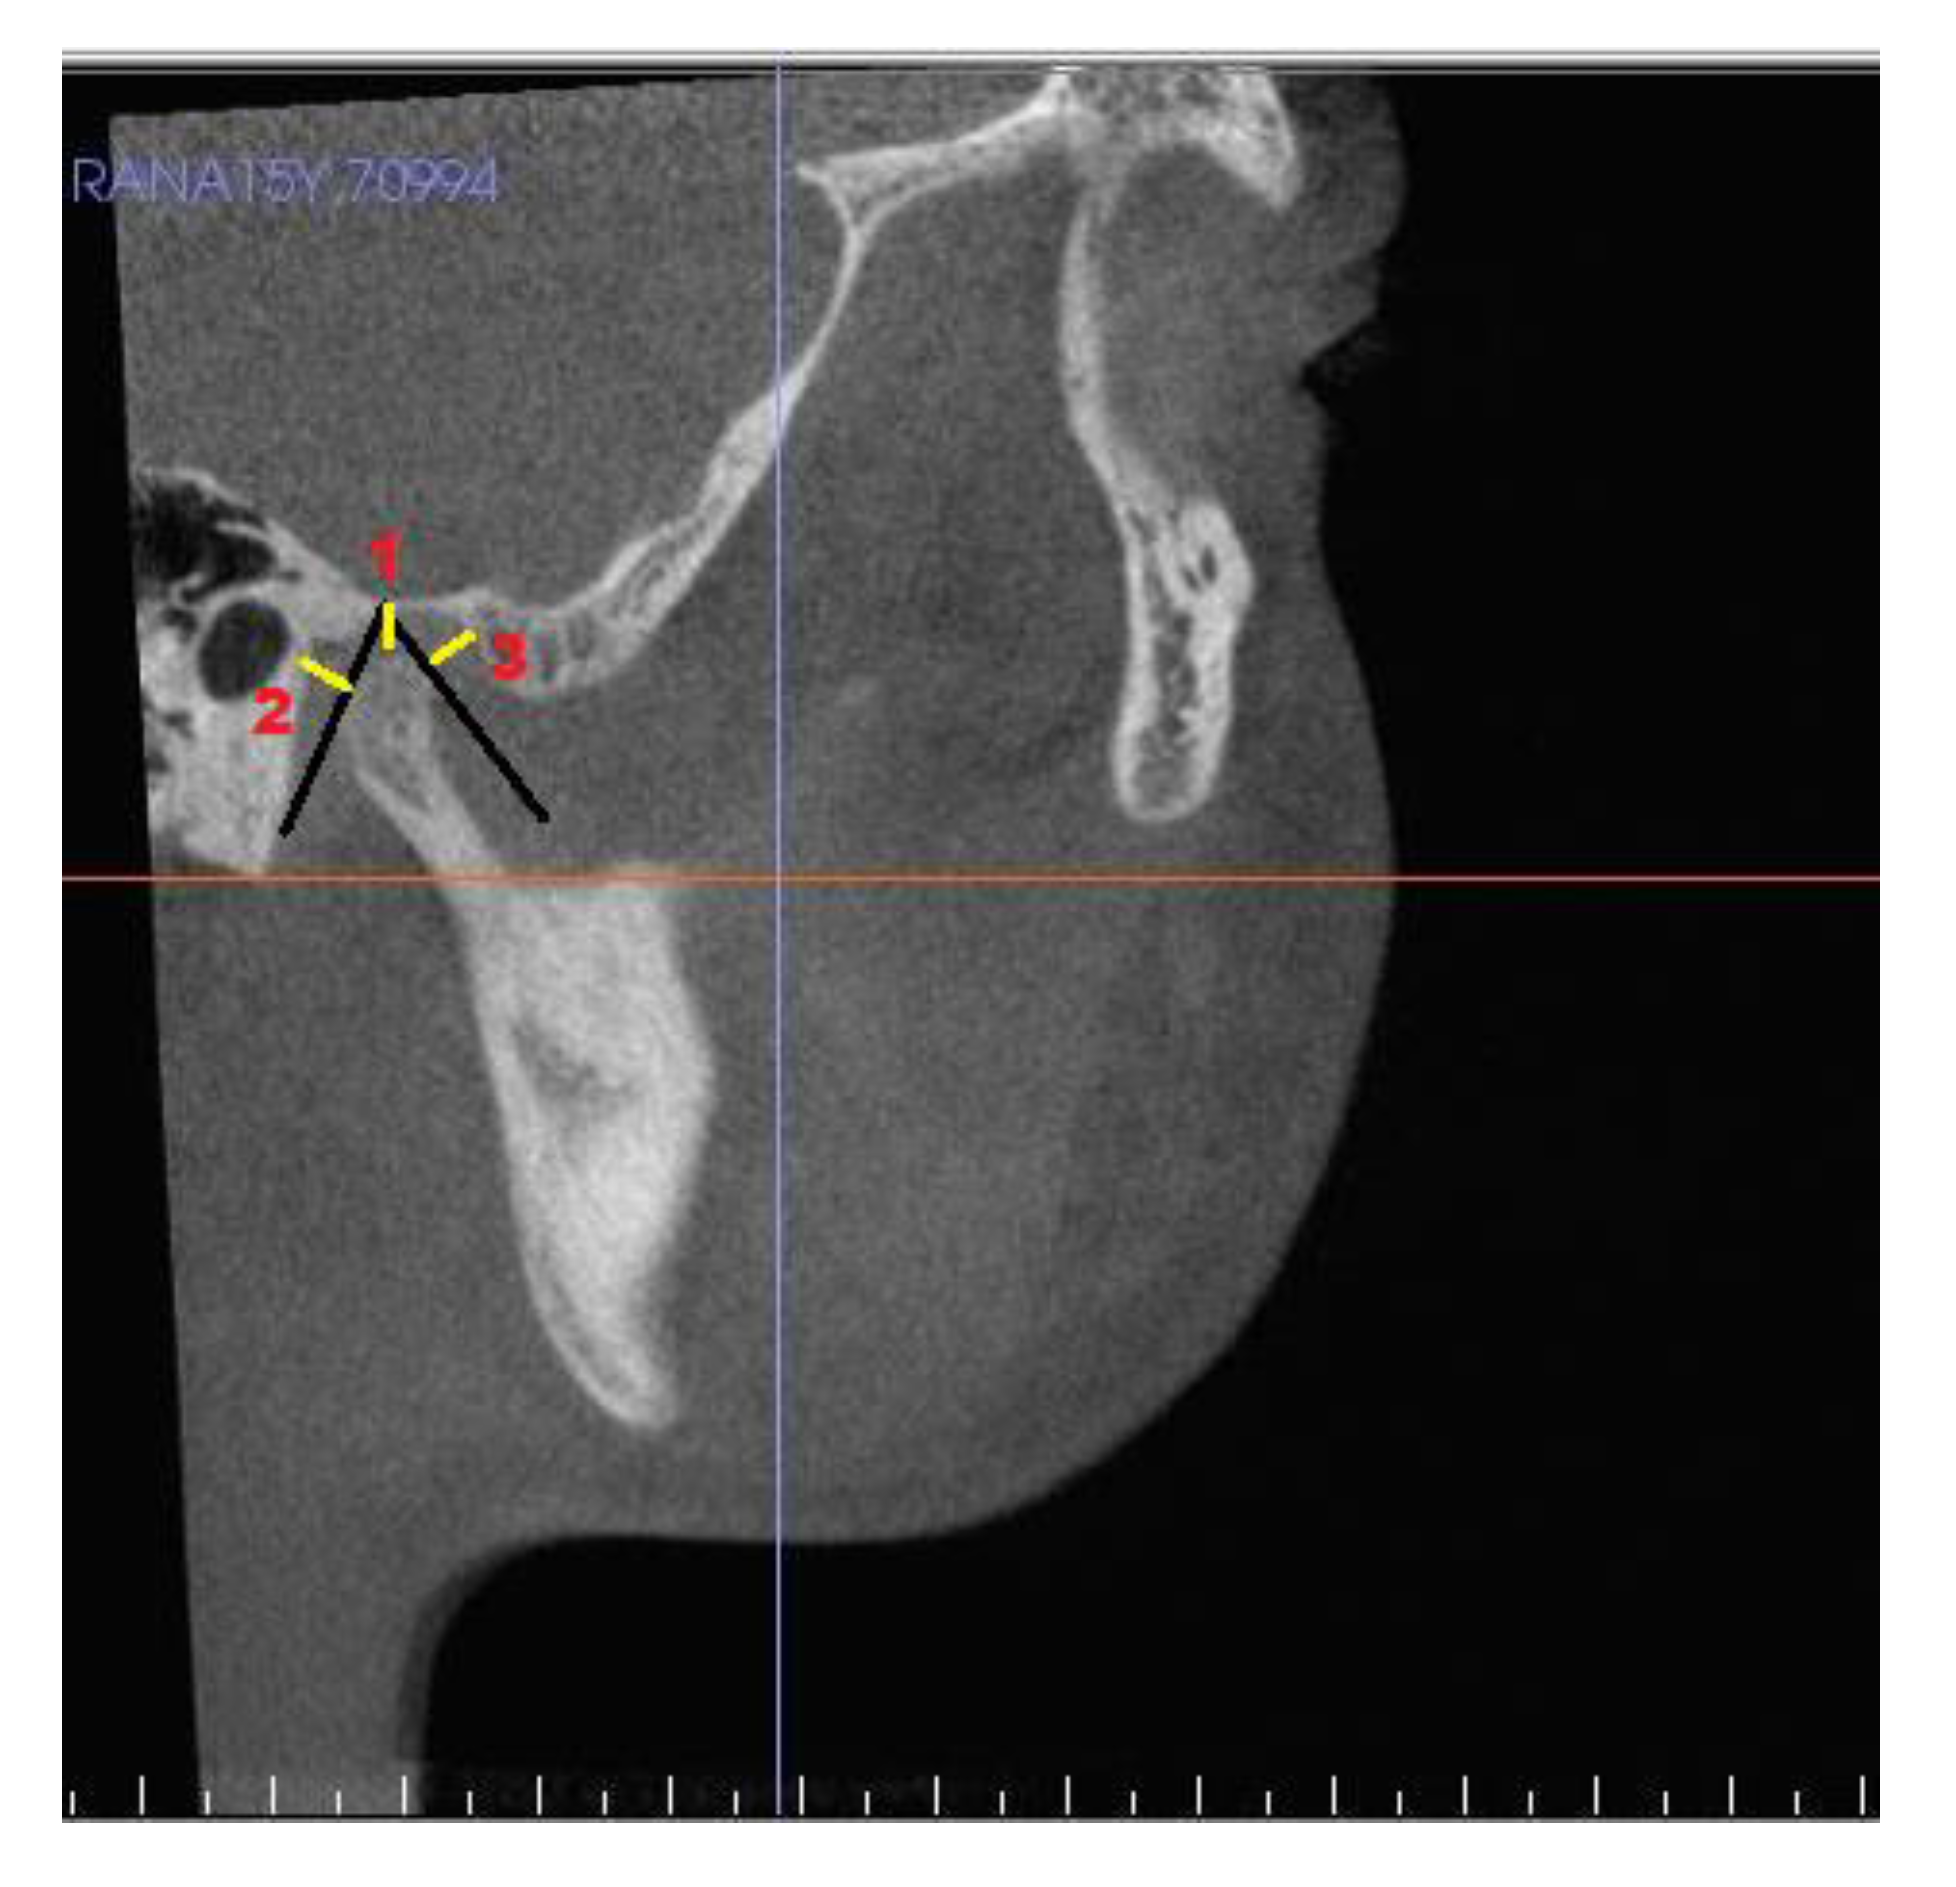

| S. No. | Measurments | Definition |

|---|---|---|

| Condyle | ||

| 1 | Superior joint space | Linear distance from superior point on condyle to highest point on glenoid fossa |

| 2 | Posterior joint space | Linear distance from posterior point on condyle to posterior surface of fossa |

| 3 | Anterior joint space | Linear distance from anterior point on condyle to a point on articular eminence |

| 4 | SCo–T vertical | Linear distance from superior point on condyle to pterygoid vertical |

| 5 | PCo–PT vertical | Linear distance from posterior point on condyle to pterygoid vertical |

| Glenoid fossa | ||

| 6 | ACo–PT vertical | Linear distance from anterior point on condyle to pterygoid vertical |

| 7 | PF 1 to PT vertical | At distance 3 mm from superior point of fossa |

| 8 | PF 2 to PT vertical | At distance 5 mm from PF1 |

| 9 | PF 3 to PT vertical | At distance 6 mm from PF2 |

| 10 | PF 4 to PT vertical | At distance 3 mm from PF3 |

| 11 | Condylar height | Distance from SCo to constructed perpendicular line. |

| 12 | Condylar volume | Volumetric analysis of each mandibular condyle after isolating it. |